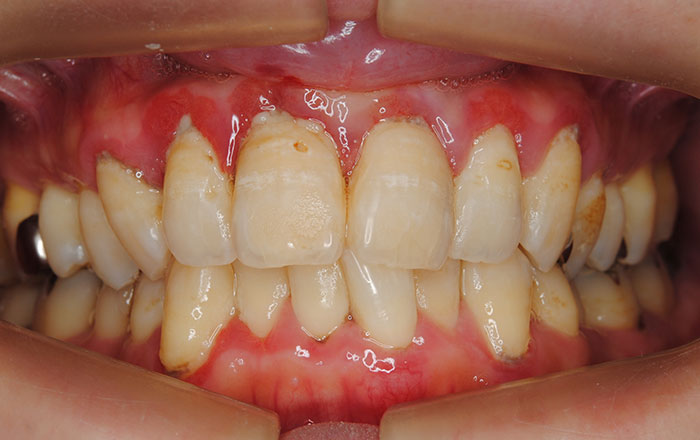

2)妊娠性歯周病になりやすい

妊娠すると歯周病にかかるリスクが増えます。

歯肉炎になると、歯茎が腫れる、歯茎から出血しやすくなるという症状が見られるようになります。

妊娠中の女性の歯周病リスクが増えるのには、女性ホルモンが大きく関わっていると言われています。

エストロゲンという女性ホルモンが、ある特定の歯周病菌の増殖を促すこと、また、歯肉の細胞がエストロゲンの標的となることで、より歯周病にかかるリスクが増えてしまいます。

これらのホルモンは、妊娠終期には月経時の10~30倍になるといわれており、妊娠中期から後期にかけて、妊娠性歯肉炎が起こりやすくなります。

ただ、虫歯と同じで、基本的にはプラークがない清潔な口の中では歯肉炎にならないか、起こっても軽度の歯肉炎で済みますので、妊娠中は特に気をつけてセルフケアを行いましょう。